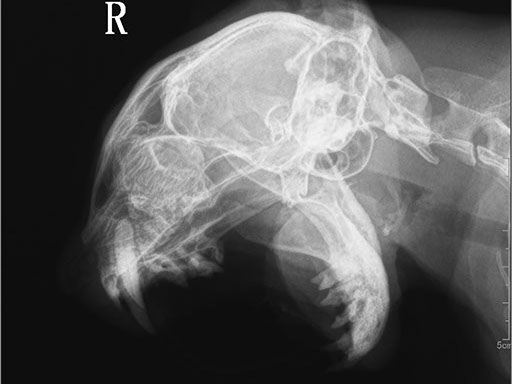

ЦИФРОВОЙ РЕНТГЕН В ВЕТЕРИНАРИИ